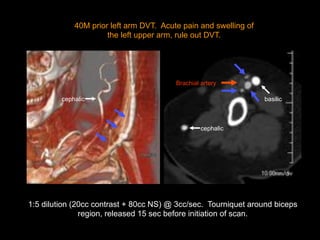

40M prior left arm DVT. Acute pain and swelling of

the left upper arm, rule out DVT.

1:5 dilution (20cc contrast + 80cc NS) @ 3cc/sec. Tourniquet around biceps

region, released 15 sec before initiation of scan.

basilic

Brachial artery

cephalic